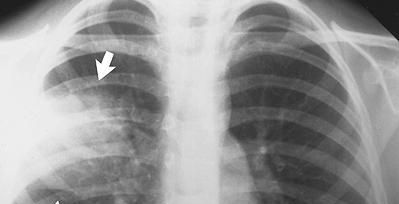

إحتفل الباحثون مؤخراً بإكتشاف طريقة جديدة للكشف المبكر عن سرطان الرئة والذي ظل إكتشافه مستعصياً على الأطباء في مراحله الأولى. ويزيد الكشف المبكر لأي نوع من الأورام السرطانية من أمل الشفاء من المرض. وبحسب مجلة "بحوث السرطان" التي صدرت منتصف الشهر الحالي فإن فريقاً أمريكياً من الأطباء والباحثين طوّروا طريقة للكشف عن سرطان الرئة بأخذ مسحة من خلايا وجنة المريض وتعريضها لضوء باهر. وأُطلق على هذه التقنية التحليلية الجديدة إسم التحليل الطيفي الموجي المجهري (PWS)، وهي تساعد على التمييز بين الأشخاص الذين يعانون من سرطان الرئة والآخرين الذين يعانون من أمراض رئوية أخرى نتجت عن التدخين لسنوات طويلة.